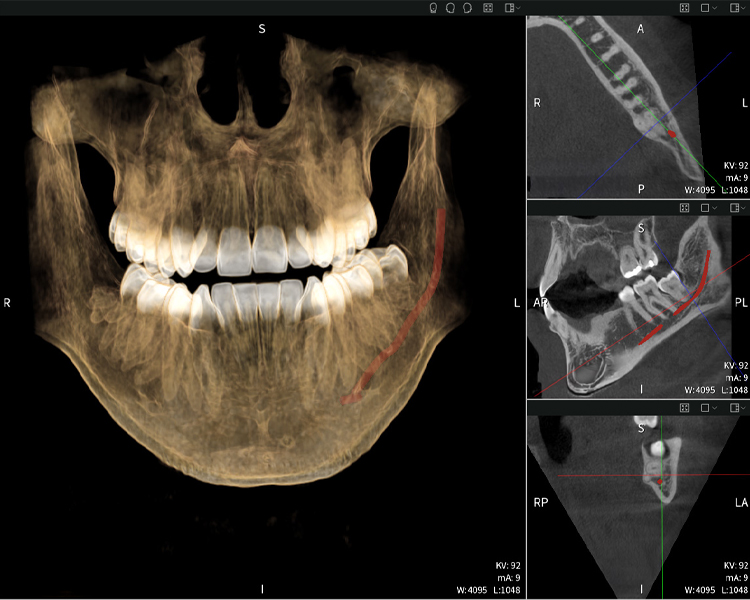

Figura e: Resultados de imagen de Seethrough Max, sobre un fondo negro.

Figura e

Figura e: La radiografía panorámica sirve como herramienta de evaluación inicial, mostrando la posición general de los dientes, así como posibles cambios patológicos. Es notable que en el lado derecho (diente 48) se observa la situación posterior a una amputación de corona realizada por un profesional externo. Las dos raíces fuertemente curvadas permanecen en estrecha proximidad topográfica al nervio alveolar inferior dentro del hueso. Esto sugiere una decisión deliberada de evitar el mayor riesgo de lesión nerviosa durante una extracción completa y representa un hallazgo clínicamente relevante. En resumen, las tomografías CBCT con Seethrough Max proporcionan información crucial sobre la anatomía compleja y la relación crítica entre las muelas del juicio y el nervio alveolar inferior. Esta imagenología diagnóstica detallada preoperatoria es esencial para realizar procedimientos quirúrgicos seguros y exitosos en la región mandibular.